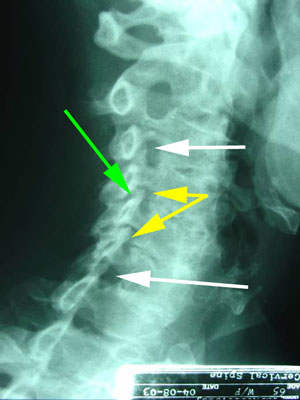

Figure 1. The green arrow shows disc degeneration, linked to causing headaches. Note the narrowing of the disc space and spurring (yellow arrows) on the front of the vertebral body compared to the normal levels above.

These changes are also called arthritis,  though the term is not technically correct for disc degeneration. However, such disc degeneration does cause arthritis in the spine joints - facet joints - that lie behind the discs.

Figure 2 shows narrowing of the nerve openings in the cervical spine - stenosis - (yellow and green arrows) compared to the normal openings above and below (white arrows). Stenosis is implicated with headaches as well as shoulder and arm pain. The pain that can extend down the arm is called radiculopathy caused by the pressure of the pinched nerve located in the narrowed nerve opening.